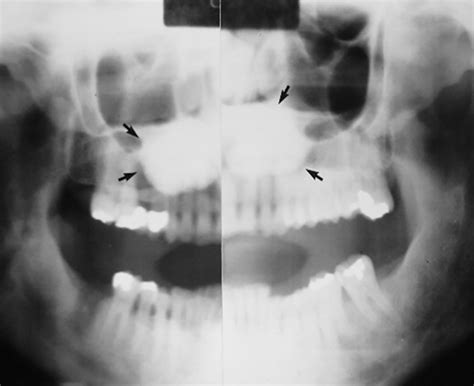

• Torus Mandibularis: These appear on the lingual (tongue-side) aspect of the lower jaw, usually above the mylohyoid line. These are often bilateral, meaning they appear on both the left and right sides of the lower jaw.